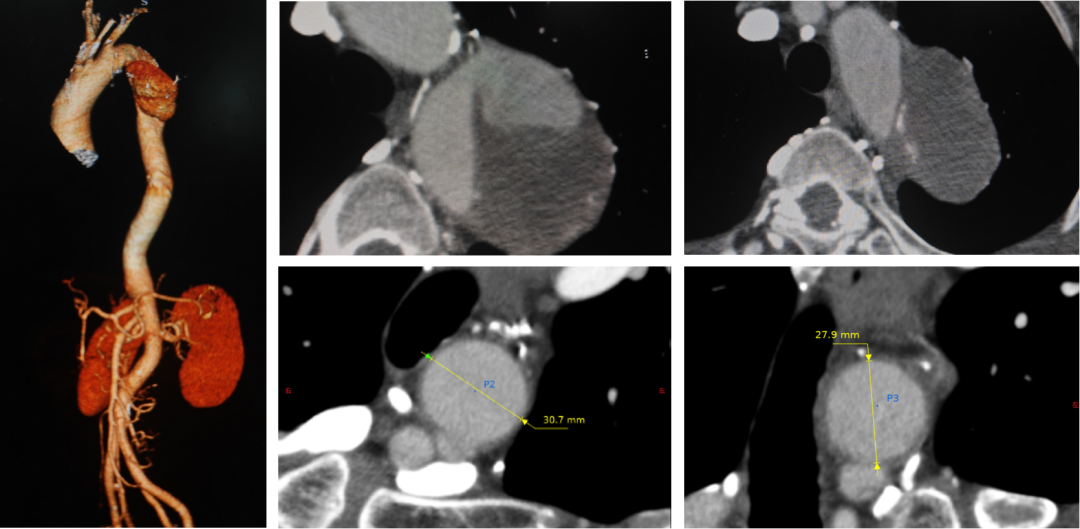

病例一(单开窗)

张XX,男,56岁,主动脉夹层。LSA单开窗。

术前